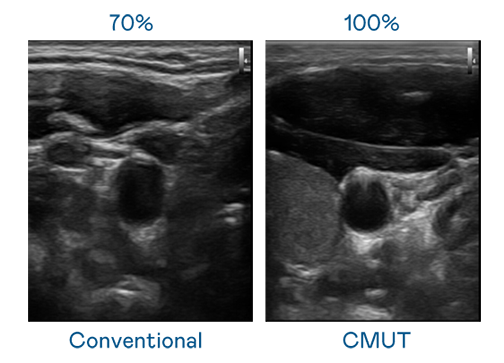

CMUT 技术是一种用电容式微机电元件来产生超音波讯号的技术。与传统 PZT 压电式技术相比,CMUT 频宽增加 30%,更宽频的超音波讯号让影像解析度大幅提升,是实现高影像品质医疗超音波扫描、促进精准医疗发展的关键技术。

大频宽带来超清晰影像

超音波影像的解析度高低,首先取决于探头能发出的讯号频宽。PA视讯 CMUT 可提供高清晰的超音波讯号,提供高频宽、高灵敏度、影像纹理细节更高的超音波影像,协助医护人员缩短影像判读时间及利用精准的医疗影像进行诊断。